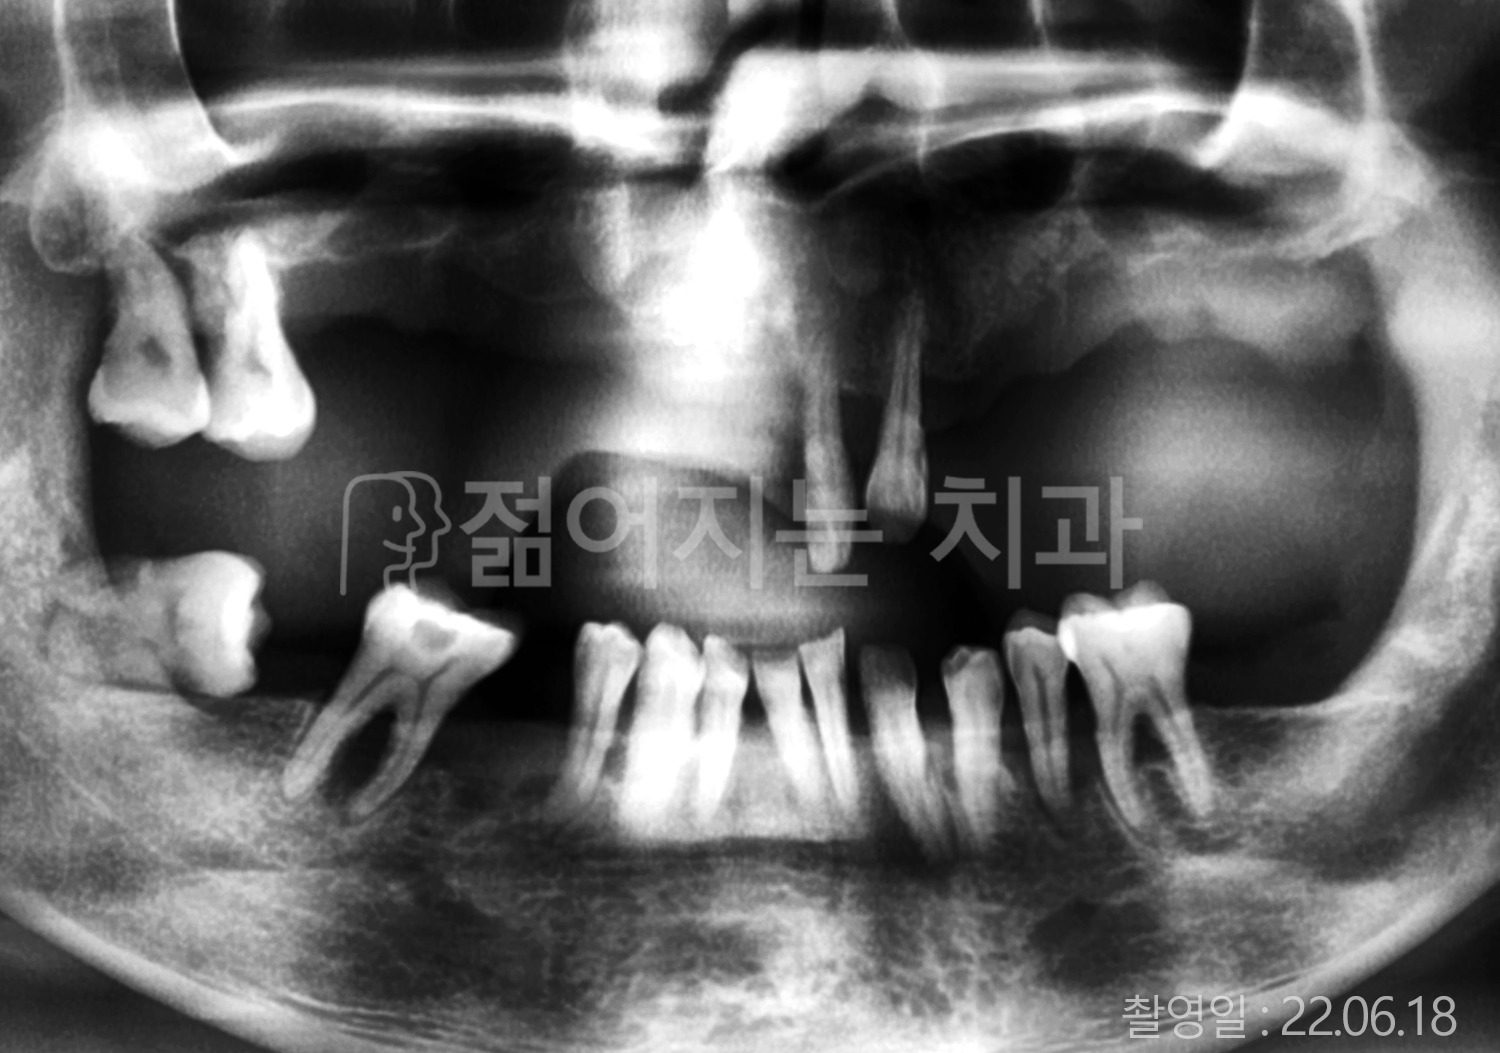

• 50대 전체치아 10개 이상 임플란트